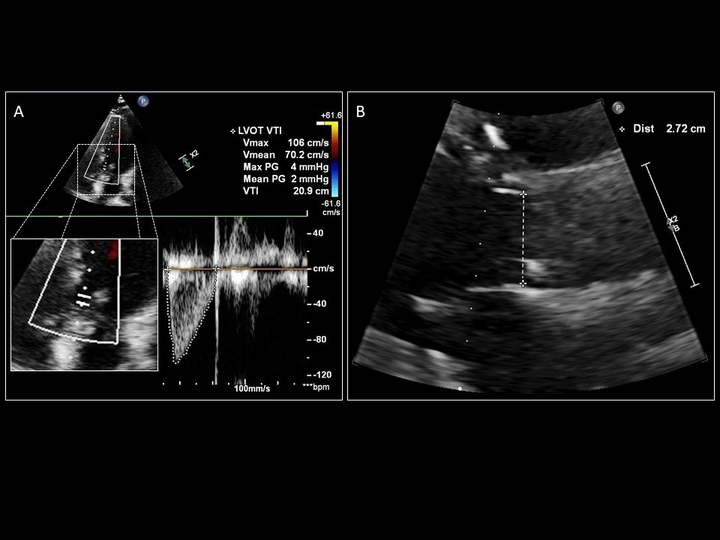

SV = CSA (cm^2) x VTI (cm) = 0.785 x (LVOTd)^2 x (LVOT VTI)

LVOT VTI generated when the Doppler line of interrogation is (A) parallel to blood flow versus (B) off-axis by greater than 20˚

Difference between an LVOT VTI obtained from an (A) appropriate sample location in LVOT with aortic valve closure captured at the end of systole, and (B) a location too proximal in the LV cavity

Demonstration of the significant difference in values obtained from over-tracing (A; 23.9cm) and under-tracing (B; 13.7cm) the same LVOT VTI.